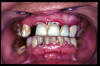

CM Caries y enfermedad periodontal avanzada